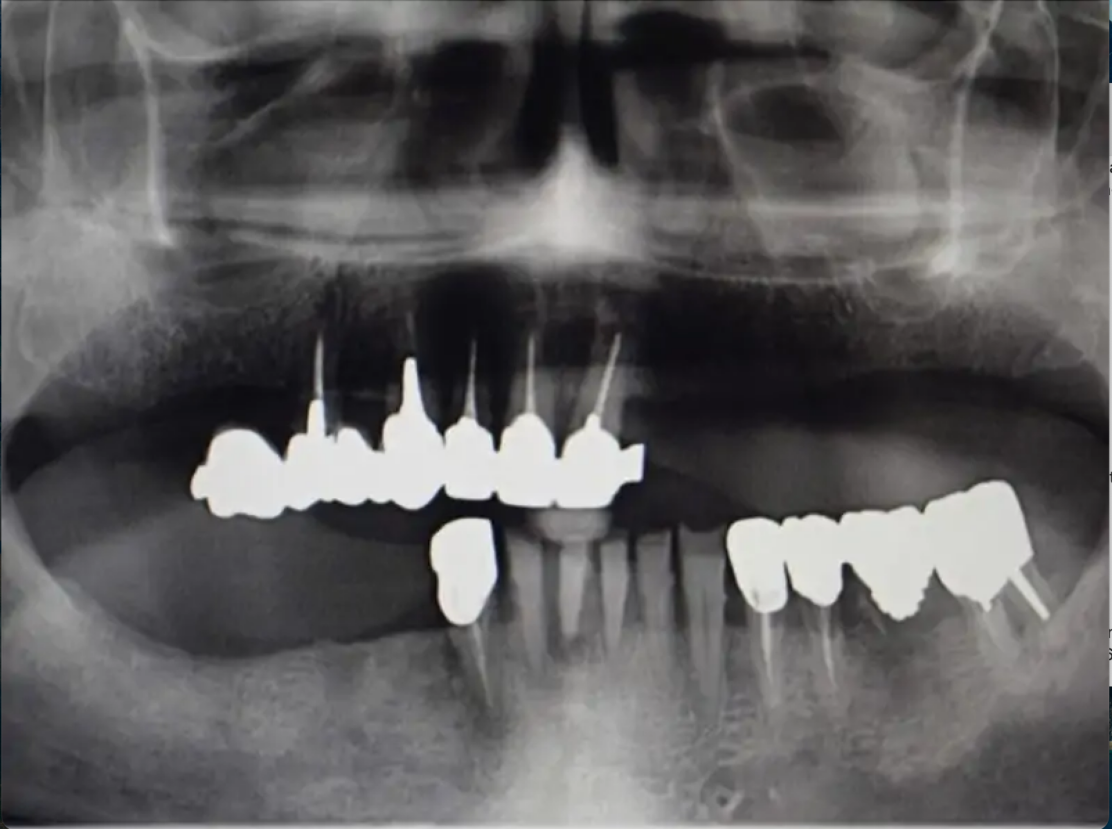

Этот пациент обратился с просьбой стабилизировать собственный протез, поэтому план лечения включал установку 4 имплантатов, на которых мы будем использовать подходящую прямую и угловую монокулярную антагонистическую кость (MUA) для стабилизации ретенционной балки, удерживающей дубликат ранее существовавшего протеза.

Чтобы минимизировать травмирование тканей, установили имплантаты безлоскутным методом, используя стопоры для точного определения длины препарирования. Сразу после операции у пациента остались заживляющие винты на имплантате и его предыдущий протез, в котором мы сделали полость внутри, чтобы избежать травмирования имплантатов. Через 5 месяцев пациент вернулся. Мы сняли слепок и изготовили дубликат протеза, который затем использовали для изготовления балки, фиксируемой поверх монокулярных альвеолярных протезов (MUA), а также внутреннего каркаса и ретенционных колпачков.